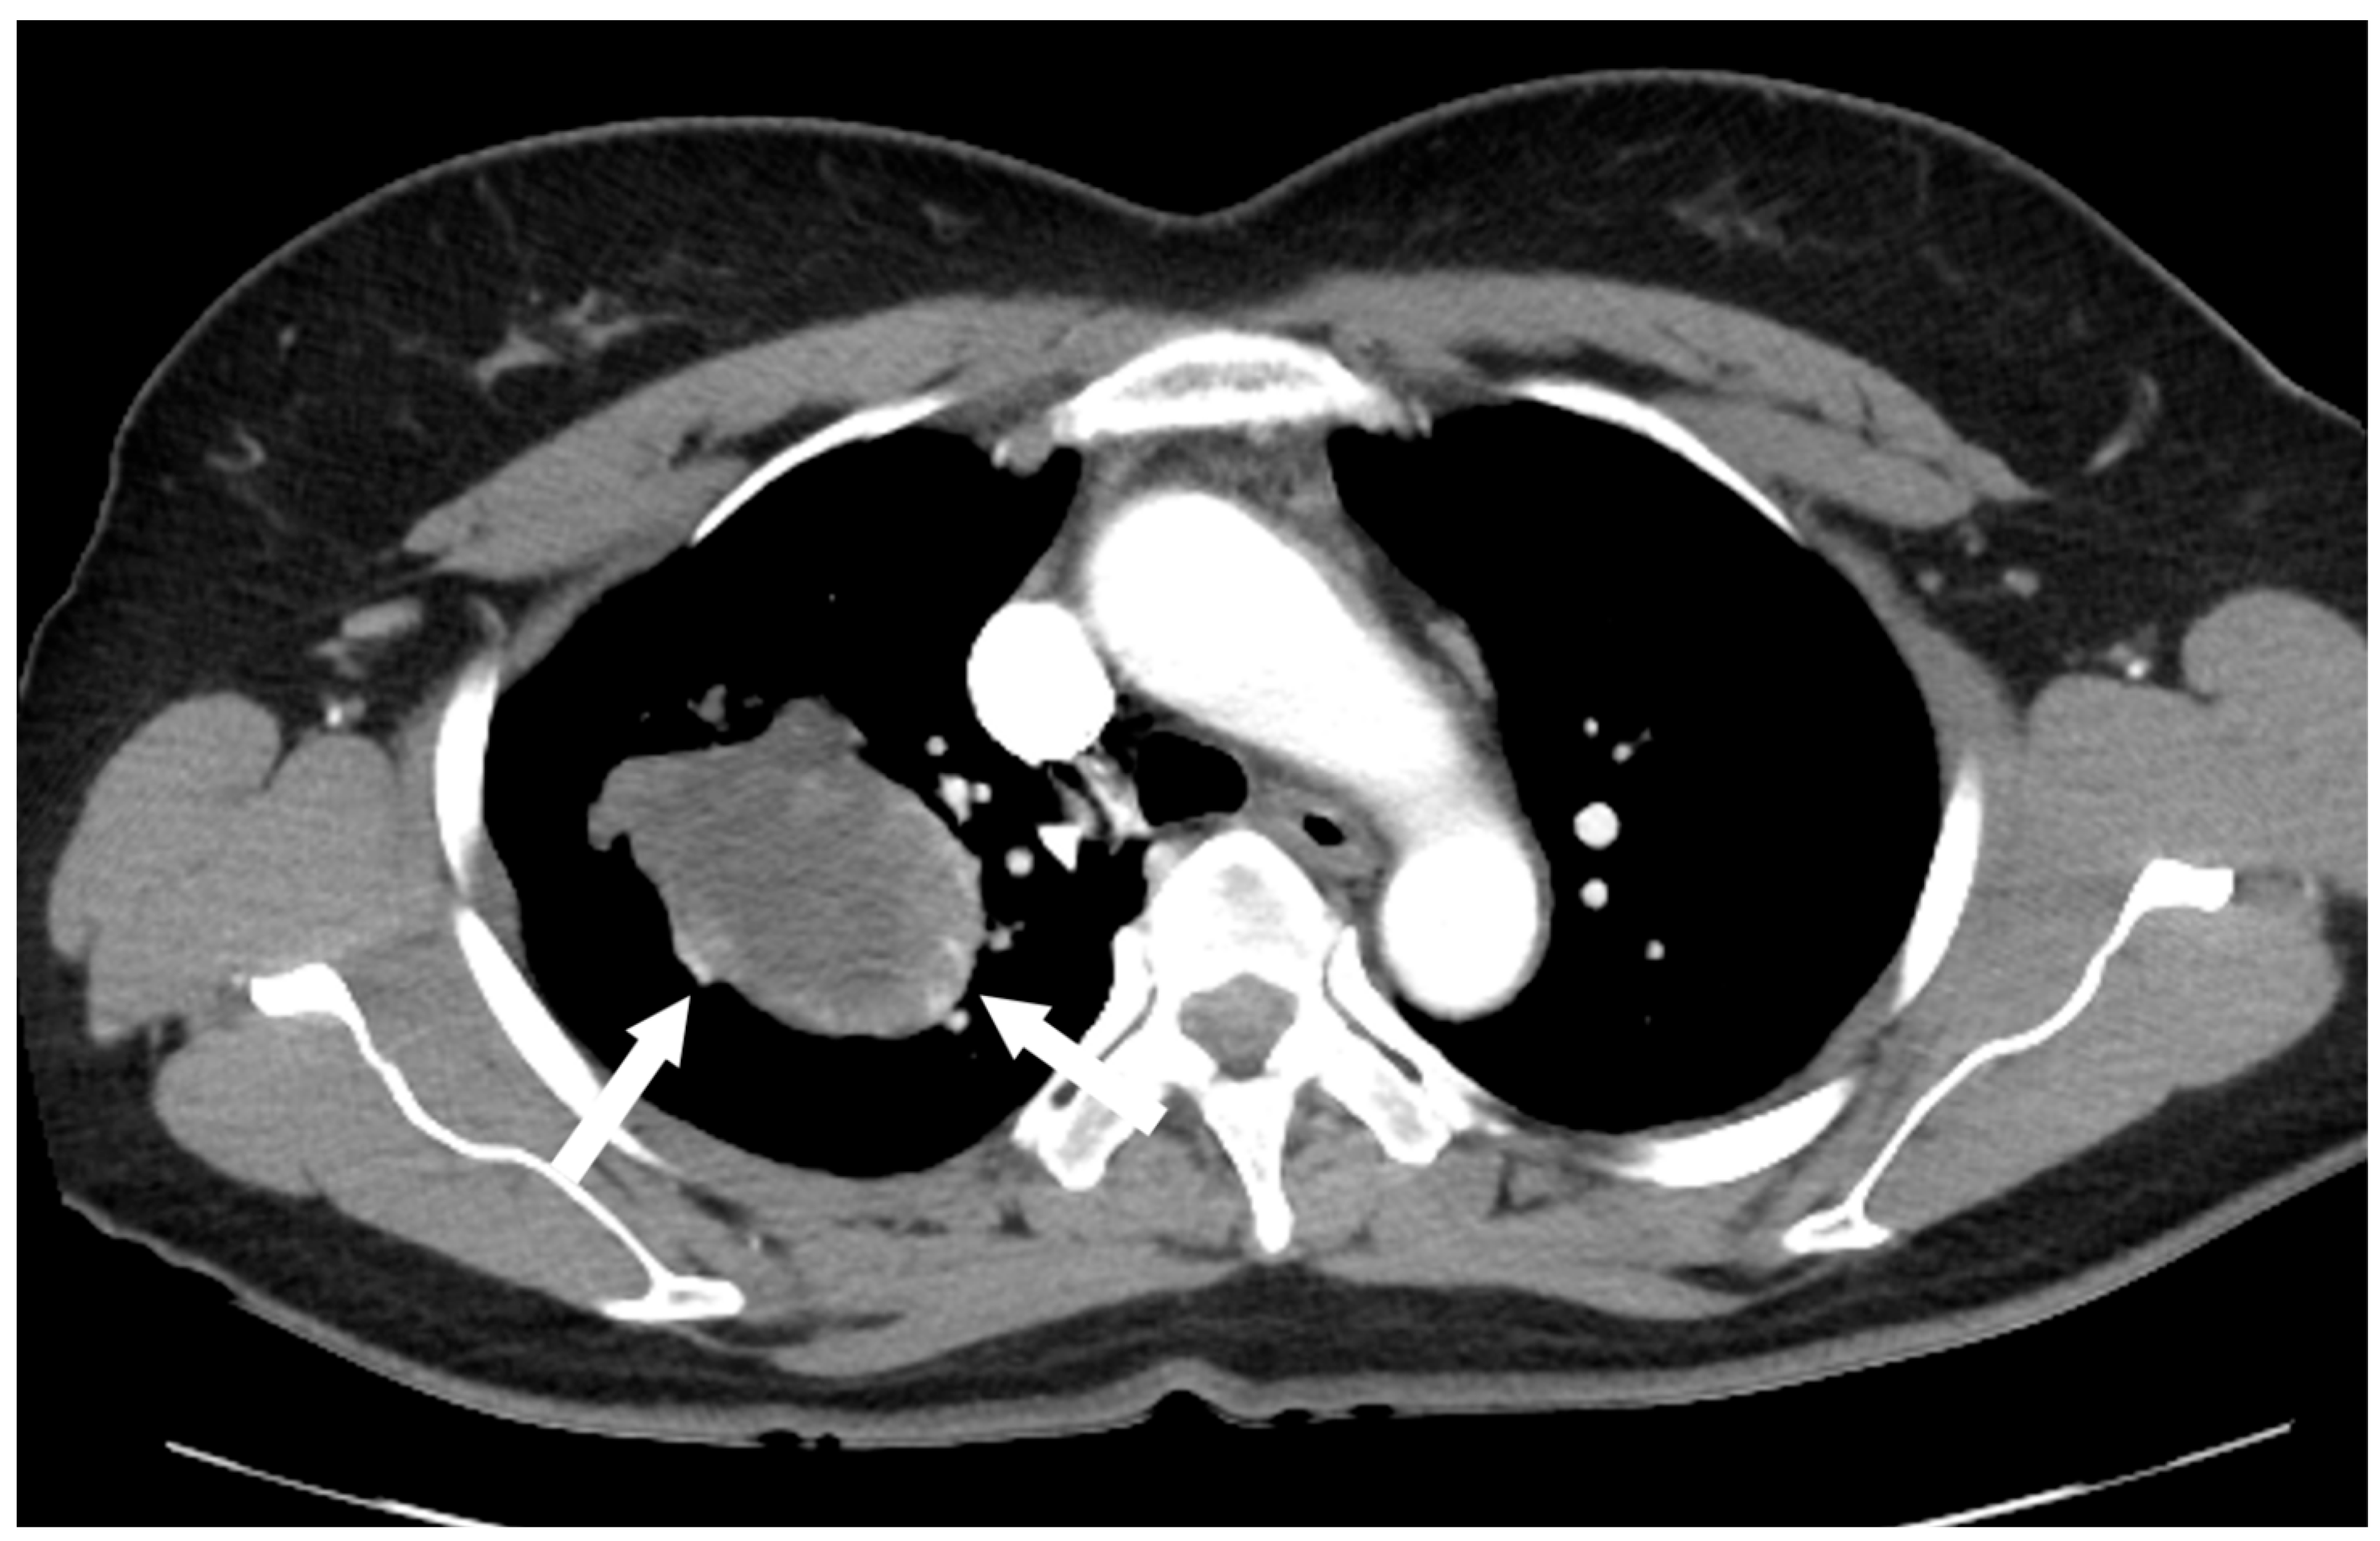

2.2. Investigations

An F-18 FDG PET/CT torso scan was performed four days after the initial CT examination to assess the metabolic activity of the mass. Surprisingly, PET/CT revealed intense FDG accumulation in the mass, with a maximal standardized uptake value (SUVmax) of 13.4, and no other abnormal lesions were detected throughout the body (Figure 4). Since the brain was not included in PET/CT, brain MRI was performed three days after the PET scan. There were no particular abnormalities on the brain MRI.

Figure 4.

PET/CT revealed intense FDG uptake in the corresponding mass in the right upper lung, with no evidence of extrathoracic involvement.

Malignant SFTs account for only 10–20% of cases. Indicators of malignancy include large tumor size (>5 cm), nuclear pleomorphism, increased cellularity, and an elevated mitotic index (>4 mitoses per 10 HPF) [2,3,6]. Imaging features suggestive of malignancy include larger size (>15 cm), compression of adjacent structures, central necrosis, ipsilateral pleural effusion, and infiltrative chest wall invasion [7,8,9,10]. In this case, the initial CT scan revealed a large mass in the lung that appeared to be a cystic lesion and did not show significant lymph node involvement, suggesting a more benign condition. However, the PET/CT demonstrated intense FDG accumulation, indicating the possibility of malignancy. As seen in this case, when coagulation necrosis and myxoid degeneration are present, the tumor may present as a non-enhancing cystic mass on a CT scan, which can lead to misdiagnosis. In such cases, evaluation of metabolic activity using PET/CT is crucial for accurate characterization.

Most intrathoracic SFTs show low-to-moderate FDG uptake in the mass on PET/CT. However, the tumor in this case exhibited high cellularity, which was suspected to have contributed to the high uptake of FDG. Although some studies have suggested that PET is not useful for differentiating between benign and malignant SFTs, avid uptake is interpreted as malignant potential.